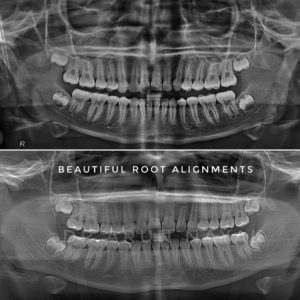

| Beautiful root alignment |